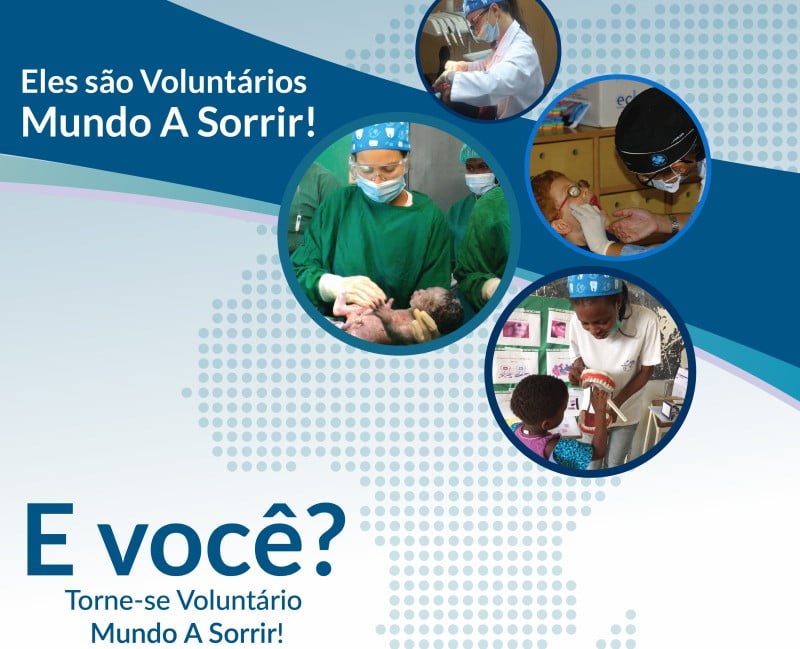

A organização não-governamental Mundo a Sorrir, que atua na área da prevenção e assistência médico dentária a crianças em situação de vulnerabilidade social, está à procura de voluntários para os seus projetos de 2018 tanto a nível nacional como internacional.